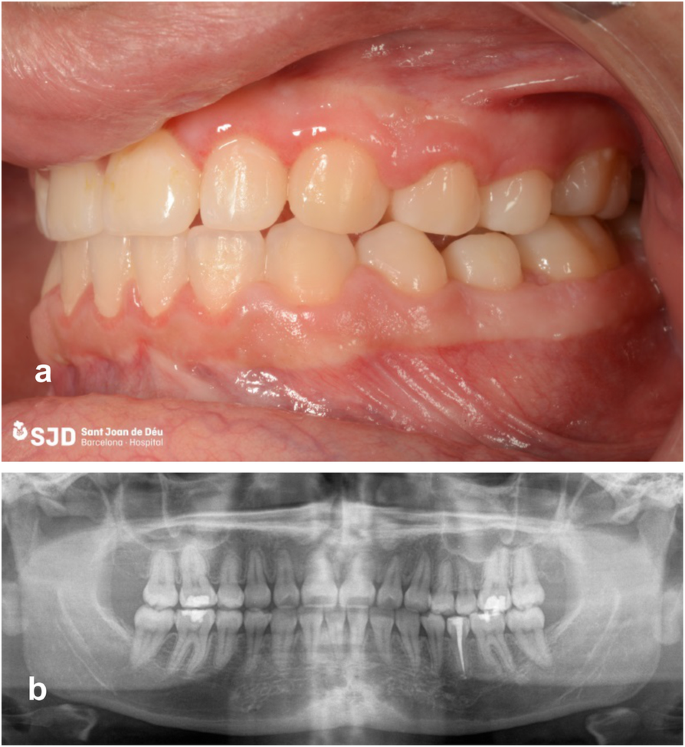

A 16-year-old patient with no medical history of interest attended the Orthodontic Service of the Hospital St Joan de Déu in due to transposition of teeth 13 and 14 (FDI notation) and persistence of tooth 75. Panoramic radiography showed tooth 35 to be impacted, in lingual direction, and oriented distally, close to the mesial root of tooth 36. Orthodontic treatment of the discrepancy consisted of the extraction of tooth 14 to allow eruption of canine 13, and extraction of tooth 75 to allow spontaneous eruption of tooth 35. However, 4 months after the extraction, tooth 35 remained in its ectopic position (Fig. 1).